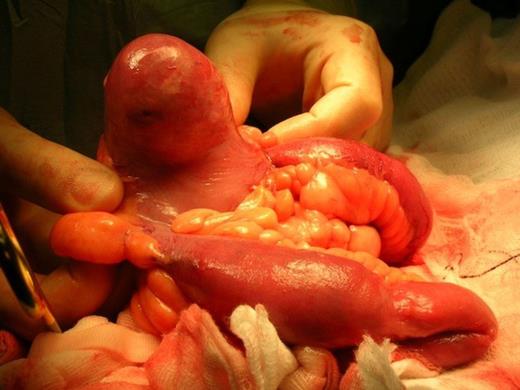

On review by the gynaecologist, clinical examination revealed a normal lower genital tract and cervix with a 12-14cm right adnexial mass and no involvement of the pouch of douglas. A transabdominal and transvaginal ultrasound scan was requested which revealed a 12 cm complex right ovarian cyst with a 3 cm daughter cyst. A CT scan was therefore requested which revealed a large cystic mass within the abdomen and pelvis with solid mural component with invasion of the uterus. There was also finding of an oval calcification in a segment of the small bowel in the left flank situated within a diverticulum with thickening of the small bowel wall at that level (Fig 1).

CT scan showing oval calcification in a segment of the small bowel in the left flank situated within a diverticulum with thickening of the small bowel wall at that level